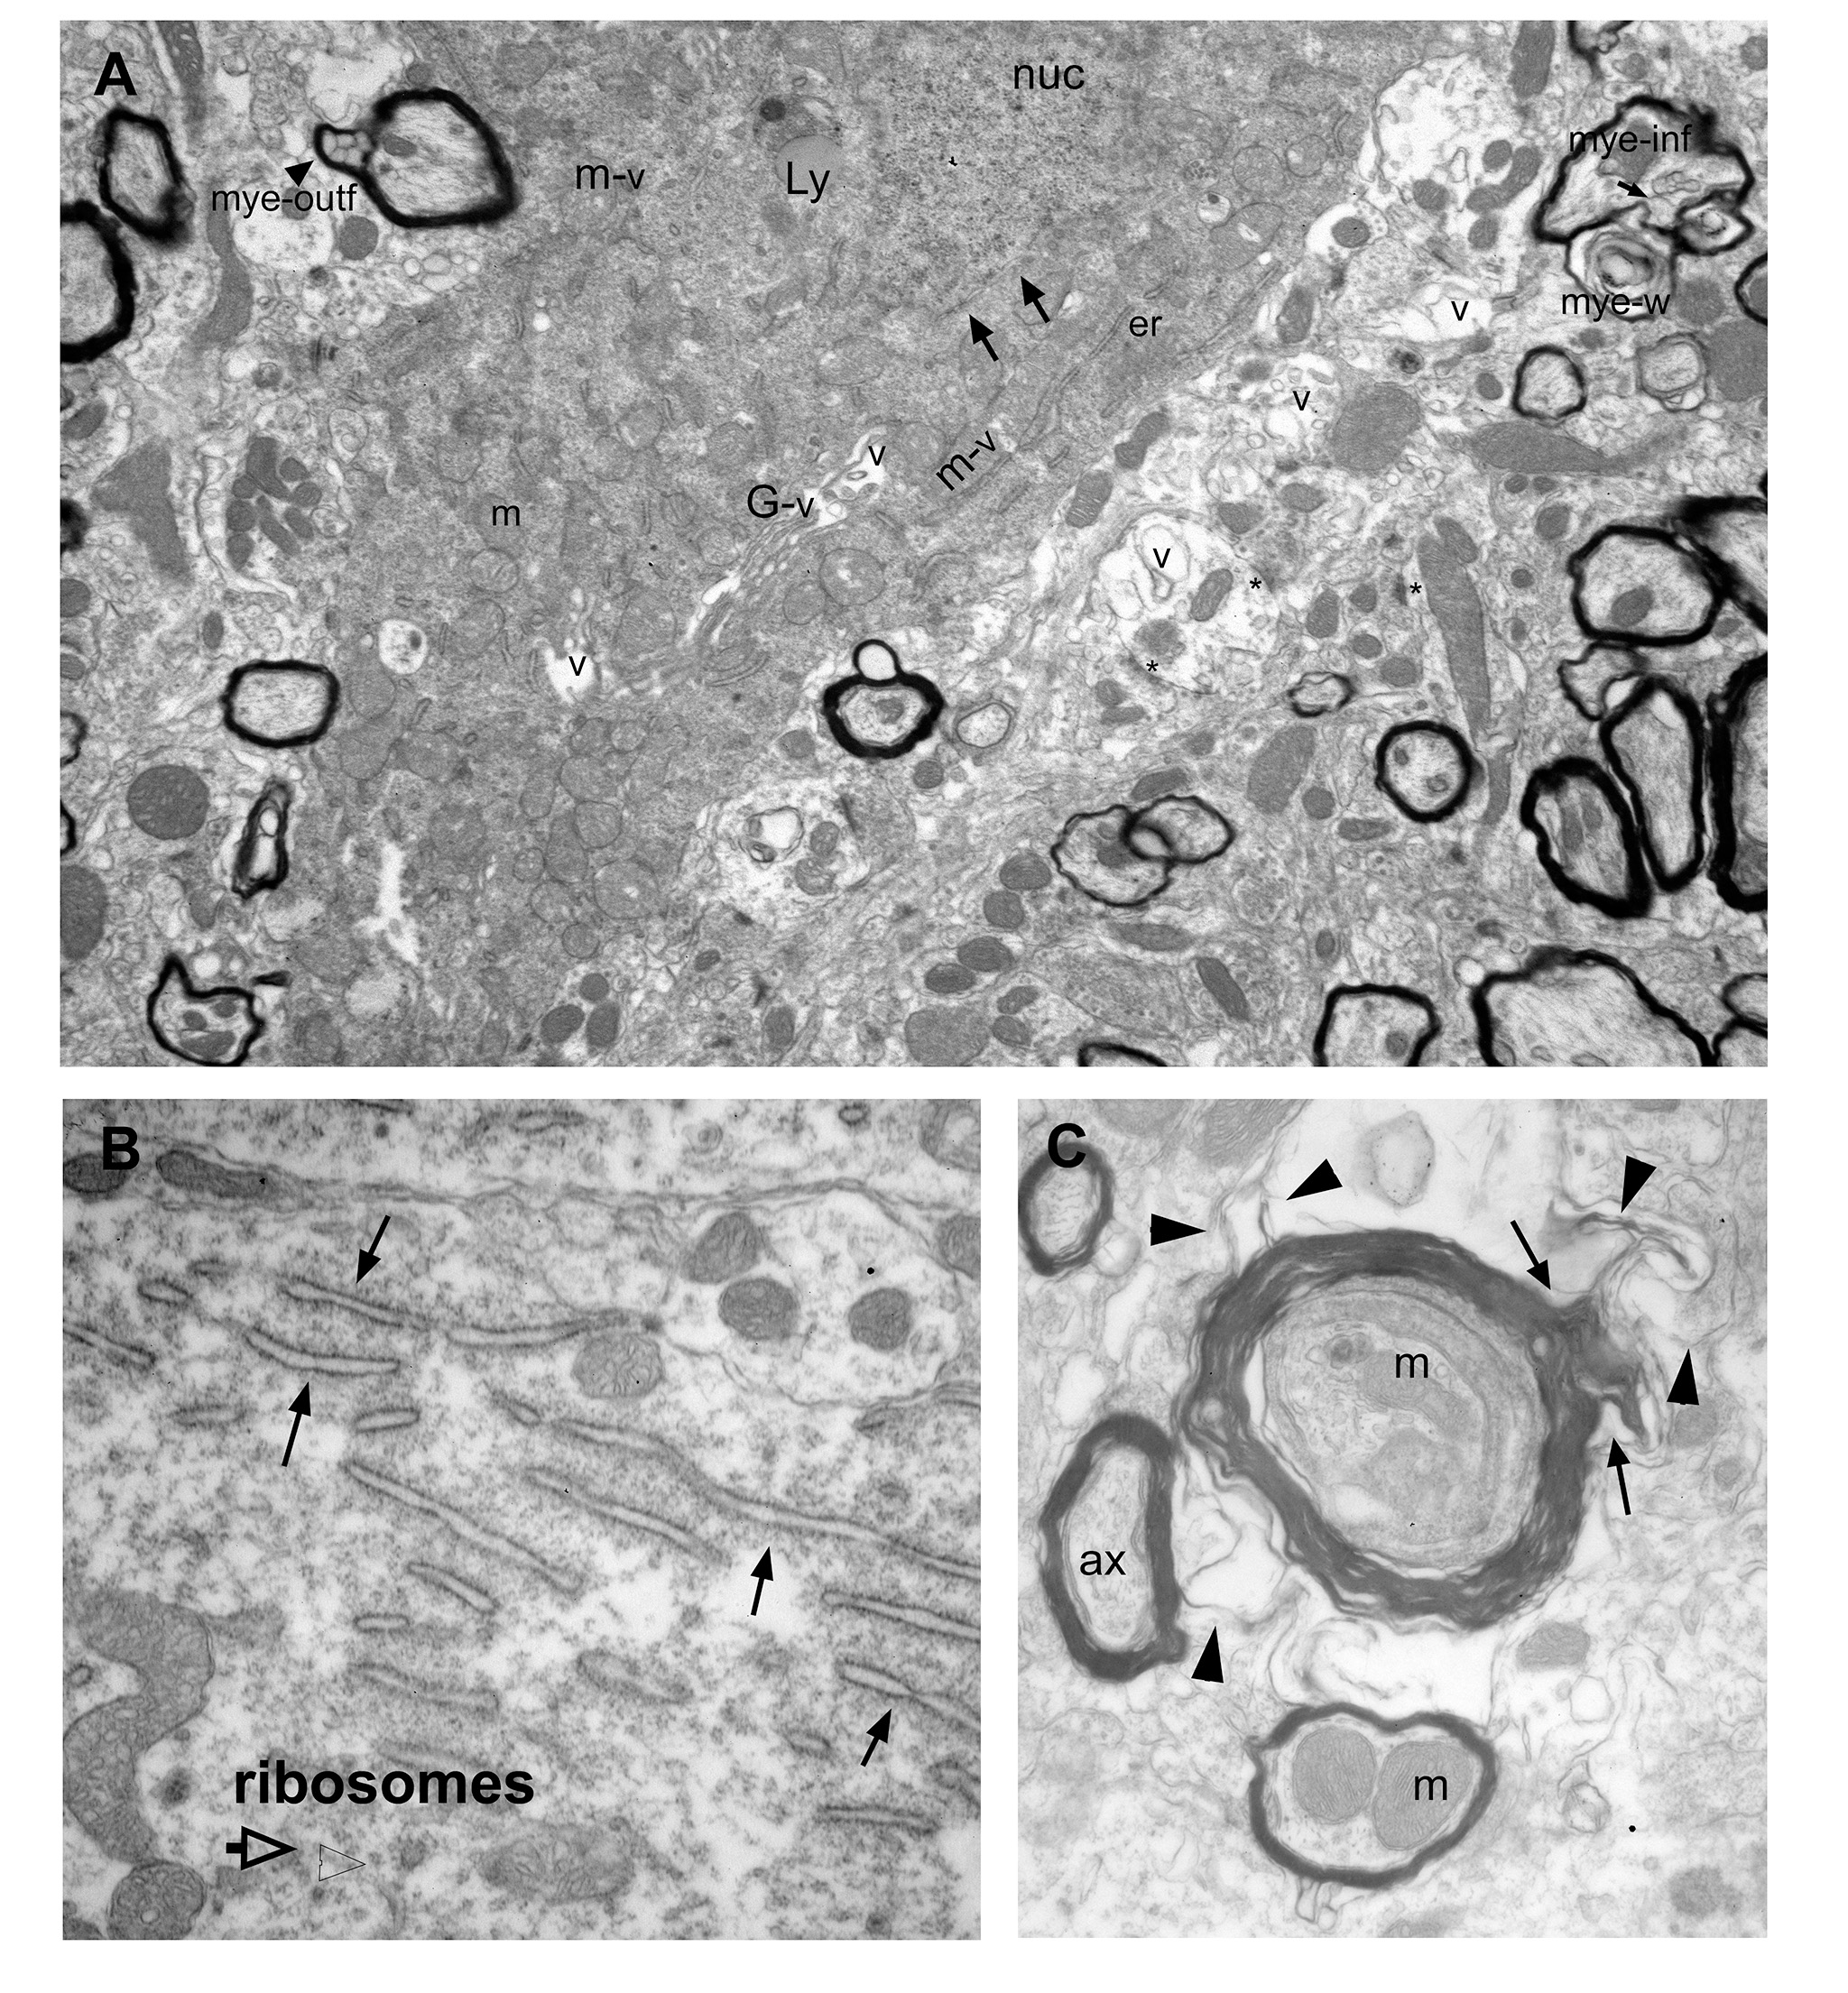

A. A cell body shows signs of cytoplasmic degeneration: Cytoplasm is electron dense; nuclear membrane is dissolved (arrows); endoplasmic reticulum (er) are sparse and display enlarged lumens; vacuoles are frequent and associated with cellular organelles including Golgi apparatus (G), mitochondria (m), and ER (er). Also note various myelination pathologies the surrounding neuropil, including myelin outfolds (mye-outf), myelin infolds (mye-inf), and myelin whorls (w). Abbrv: nuc: nucleus; Ly: Lysosome.

B. ER stress is characterized by the enlargement of its lumen (arrows). This cell is otherwise healthy, with free and ER-associated ribosomes int he cytoplasm.

C. Examples of myelination pathologies frequently encountered in the basal forebrain in PM3 brains. In this example, thick myleing surrounds a collection of neuropil components including membranes, mitochondria, and multivesicular bodies. The myelin sheet gives off a filamentous outfold (arrows), which invades the surrounding neuropil (arrowheads).